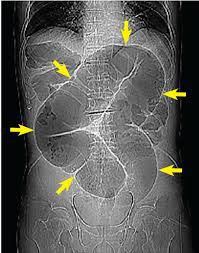

The coffee bean sign is a classic conventional radiographic finding of sigmoid volvulus. As the closed loop of the sigmoid colon distends with gas, apposition of the medial walls of the dilated bowel form the cleft of the coffee bean, while the lateral walls of the dilated bowel form the outer walls of the bean.